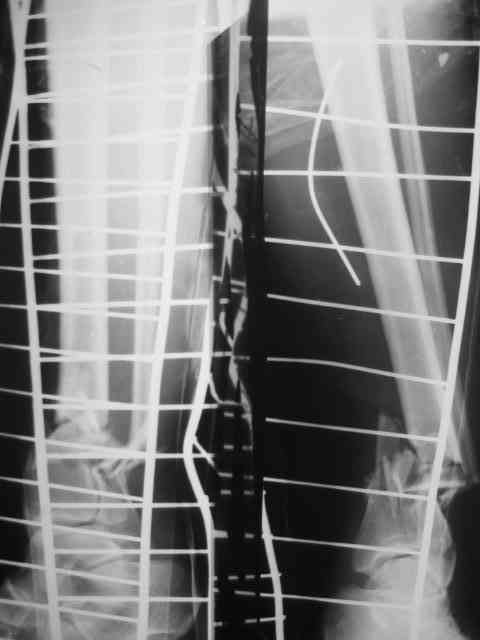

Здравствуйте коллеги! Вышел с отпуска и в палате оказалась данная

пациентка. Из истории выяснилось: травма 29.01.07 Диагноз: Открытый

оскольчатый перелом н/3 костей голени (якобы 2 Б Каплан), при

поступлении операция из трех букв и скелетное вытяжение + остальная

терапия. Затем выполнили остеосинтез штифтом (по ходу, Эксперт стоит)

видимо хотели  зацепится за дистальный отломок, но скорей всего все

было нестабильно и накинули этот  сокращенный АВФ. На сегодня (162

дня): Больная ходит с ограниченной нагрузкой на конечность  (трость).

Движения в г/стопе качательные. Трофика мягких тканей не

настораживает.  Воспаления м/тканей нет. В планах: 1. удаление штифта

2.Наложение стандартного АВФ с фиксацией стопы и устранение всех

смещений 3.Резекция нежизнеспособных костных отломков 4.Остеотомия в/3

большеберцовой кости с последующей дистракцией и замещением дефекта.